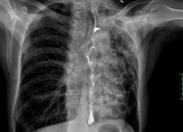

食管大部分位于后縱隔內(nèi),其上端和下端比較固定,而中間可以移動(dòng)。食管在其行程中經(jīng)過和跨越許多結(jié)構(gòu)和器官。附近結(jié)構(gòu)和器官的病變可以機(jī)械地影響食管,造成外壓和牽拉,從而出現(xiàn)異位和變形,嚴(yán)重時(shí)可導(dǎo)致咽下困難。因此,食管的位置和管腔形態(tài)的變化在一定程度上反映鄰近組織和器官病變的性質(zhì)和程度。

- 常見癥狀:胸痛、不能進(jìn)食、面色蒼白、血壓下降